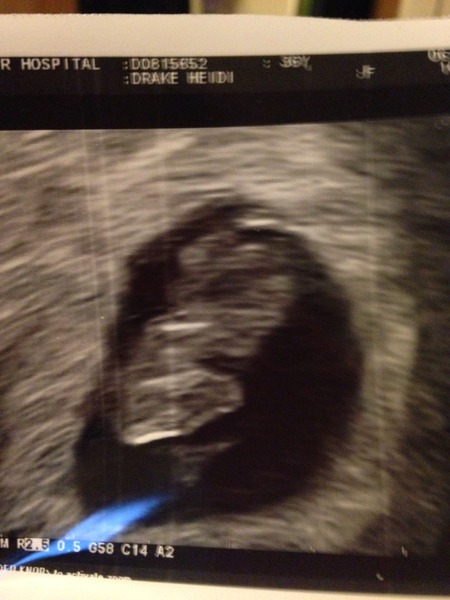

Hopefully picture will appear here. It's a photo of the scan so not great quality. Best bit was seeing the heart beat - so quick and strong!Grin

Donna what a lovely scan pic :) Bet you're over the moon.

DoctorDonnaNoble · 07/02/2015 07:18

I will admit to tears of relief!